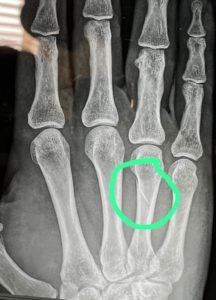

Durante el transcurso del CSN3*que tuvo lugar la semana pasada en Hípica de Toledo, Mireya Ramírez sufrió una fractura en su mano mientras disputaba una prueba.

Ante el interés de la amazona de

poder correr la Final de la Liga de salto de la RFHE que se llevará a cabo este fin de semana en las mismas instalaciones, fue a visitar al traumatólogo de los jinetes, Jaime Baselga.

Éste encontró una solución transitoria para que pudiera disputar el concurso de esta semana. La importancia de que el traumatólogo entienda de este deporte es que siempre apuesta por la carrera deportiva de los jinetes.

El lunes de la semana que viene, cuando ya haya finalizado el concurso, Mireya visitará a Jaime Baselga en su consulta de Madrid para determinar el correcto tratamiento para su mano en los próximos días para asegurar una recuperación absoluta que la permita continuar con su carrera deportiva.